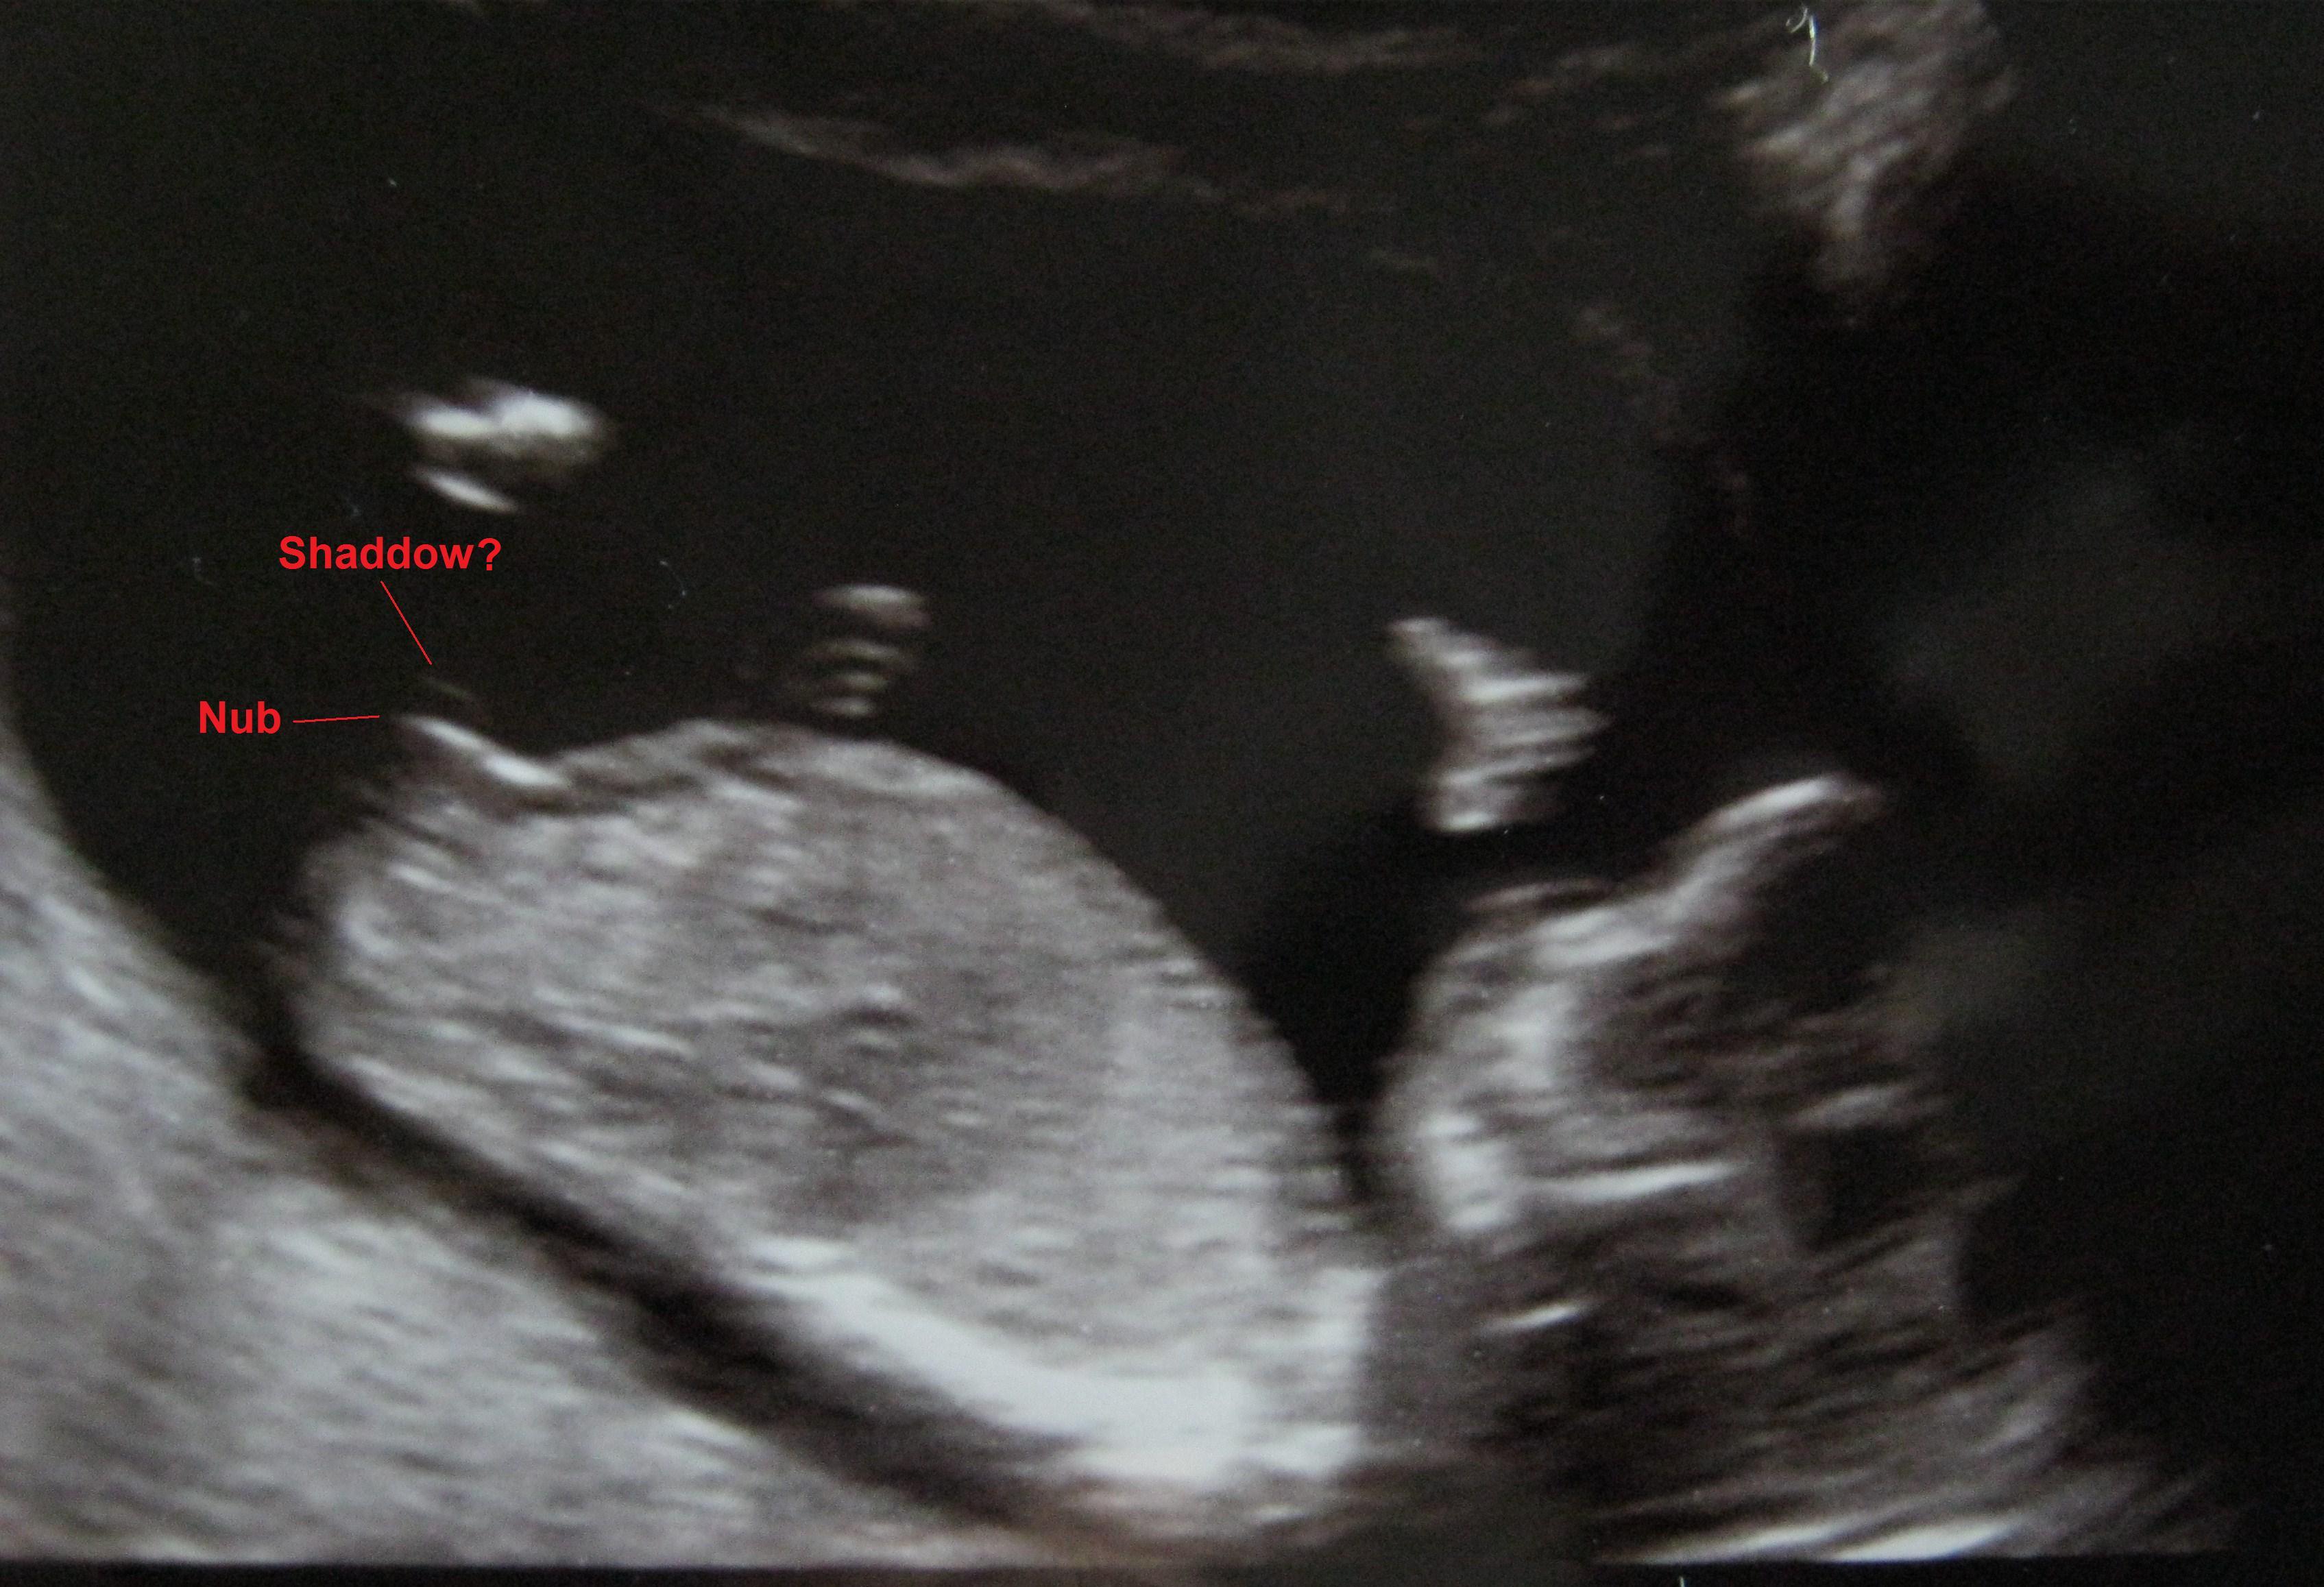

14 week and 1 day ultrasound pic- Nub 'shadow'???